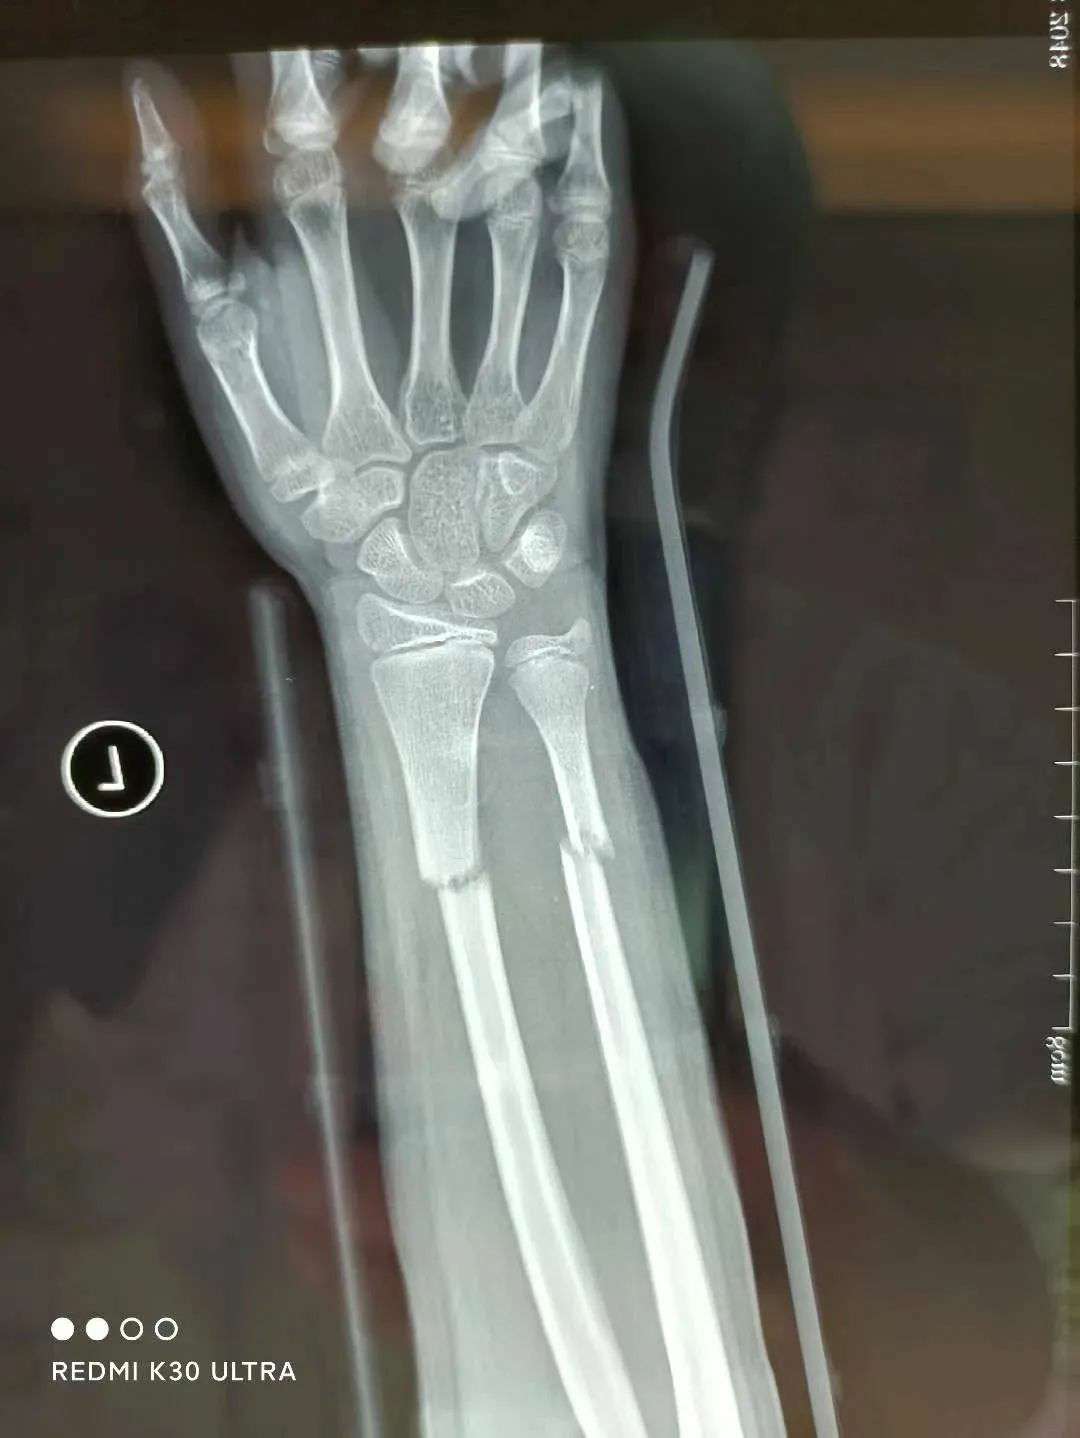

患者39岁,因外伤导致左手疼痛难忍,前来福清市第五医院中医骨科门诊寻求治疗。经过详细检查,患者被确诊为左侧桡骨远端粉碎性骨折伴下尺桡关节脱位。接诊的王征勇运用精湛的正骨手法进行复位,并在中医正骨理论的指导下,使用石膏进行固定。这种治疗方案有效地稳定了复位后的桡骨远端骨折,促进了骨折的愈合,避免了不必要的手术治疗,同时显著减轻了患者的疼痛感。

复位前

复位后